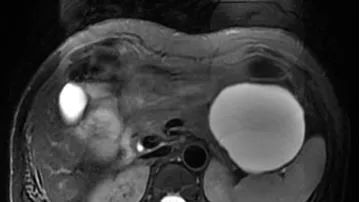

卵巢肿瘤的影像学表现及鉴别 医学界影像诊断与介入频道 · 公众号 · 医学 · 7 年前 · |

胰腺病变的MRI诊断思路 医学界影像诊断与介入频道 · 公众号 · 医学 · 7 年前 · |